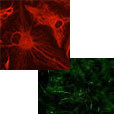

共培養モデル・神経炎症モデル (ミクログリア × アストロサイト × 神経細胞)

ミクログリア x アストロサイト x 神経細胞の3者共培養により、脳内環境を再現し、神経炎症カスケードの可視化や、Ca2+イメージングにて神経活動評価が可能です。

| 2024 | NEURO2024 (第47回日本神経科学大会) | Study of glial function on neuronal activity under neuroinflammation in neuron/astrocyte/microglia tri-culture system (H. Kobayashi, H. Kato, S. Endoh-Yamagami) | 神経炎症は様々な神経変性疾患に関与し、ミクログリアやアストロサイトのようなグリア細胞が中心的な役割を果たすことが知られている。本研究ではiPS細胞由来の神経細胞、アストロサイト、ミクログリアを用いた三者共培養系を用いて神経炎症を再現し、神経活動に対する神経炎症やグリア細胞の影響を評価した。本研究成果は神経炎症関連疾患の病態理解に有用なものである。 | |

| 2023 | Society of Neuroscience | 2D and 3D tri-culture systems for investigation of cellular interaction among neurons, astrocytes, and microglia (Hayato Kobayashi, H. Kato, Setsu Endoh-Yamagami) | 脳は神経細胞とグリア細胞 (アストロサイト、ミクログリア、オリゴデンドロサイト) から構成され、脳機能や病態形成にはこれらの細胞の相互作用が重要である。本研究ではiPS細胞由来神経細胞、アストロサイト、ミクログリアの三者共培養系を構築し、神経炎症誘導によるミクログリアの形態変化や、ミクログリアとアストロサイトの細胞間相互作用を確認した。本培養系は、中枢神経系の細胞間相互作用の評価を可能とし、脳の本来の機能や病態形成の研究に大きく役立つことが期待できる。 | |

| 2023 | 第46回日本神経科学大会 | 2D and 3D tri-culture system composed of hiPSC derived neurons, astrocytes, and microglia (H. Kobayashi, H. Kato, S. Endoh Yamagami) |

神経変性疾患に深く関与する神経炎症において、ミクログリアの役割が注目されている。iPS細胞由来ミクログリア単独培養では、活性化状態に特徴的なアメボイド型を示したのに対し、アストロサイトや神経細胞と共培養することにより、ミクログリアが健常者のヒト脳内に近い多分岐型の形態を示した。また、炎症刺激であるLPSにより、3者共培養中のミクログリアが多分岐型からアメボイド型へと変化すること、さらには、LPS刺激による細胞の活性化が、ミクログリアからアストロサイトへ伝えられていくことを示した。神経炎症の理解に貢献することが期待できる。 | |